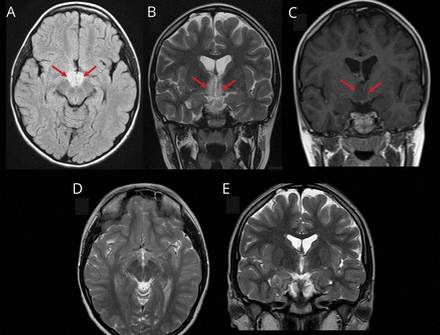

一名10岁女孩出现了15天的日间过度嗜睡和突然入睡、睡前幻觉、低食欲和行为改变的病史。脑部核磁共振检查显示双侧下丘脑病变(数字).我们发现血清中AQP4 -IgG抗体阳性,脑脊液中下丘脑泌素水平低(93 pg/mL)。诊断为继发于视神经脊髓炎谱系障碍的发作性睡病。服用糖皮质激素后病情好转。接受硫唑嘌呤免疫抑制维持治疗10个月后,随访神经影像学无新病变。任何间脑性临床综合征,如伴有下丘脑累及的嗜睡症,都应提示进行血清AQP4 -IgG检测。1,2

脑部核磁共振成像

症状2周后的脑MRI, (A)轴向液体衰减反转恢复成像和(B)冠状位t2加权图像显示双侧下丘脑高强度非强化病变(C)(箭头)。(D)和(E) t2加权图像显示诊断和治疗3个月后病变的分辨率。